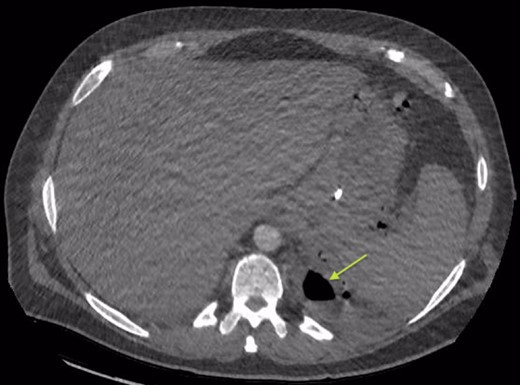

An Intercostal drain was inserted under CT-guidance aiming to decompress the pleural space. Amylase level in the pleural drainage was 880 U/l, Lipase 472 U/l. There was significant reduction of the Hydropneumothorax (Fig. 5). Given his young age, potential for loss of lung volume and infection he proceeded to decortication.

Sagittal view CT Chest post-intercostal catheter drainage of the Pancreatico-pleural fistula. Smaller residual space can be noted compared to Image 3, with some ongoing loss of lung volume and small fluid collection.